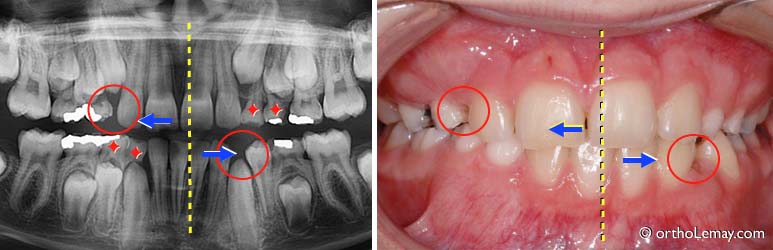

(A) Garçon de 6 ans avec un maxillaire supérieur étroit. En fermant la bouche, la mandibule est alignée avec le haut (ligne bleue).

(B) À la fin de la fermeture, une interférence entre les canines de droite (cercle) fait dévier la mandibule vers la droite en occlusion croisée. L’expansion maxillaire rapide permettra de corriger cette déviation.